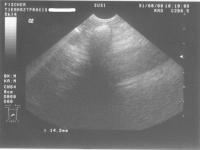

Ultraschallbilder:

Ultraschall1 Ultraschall2